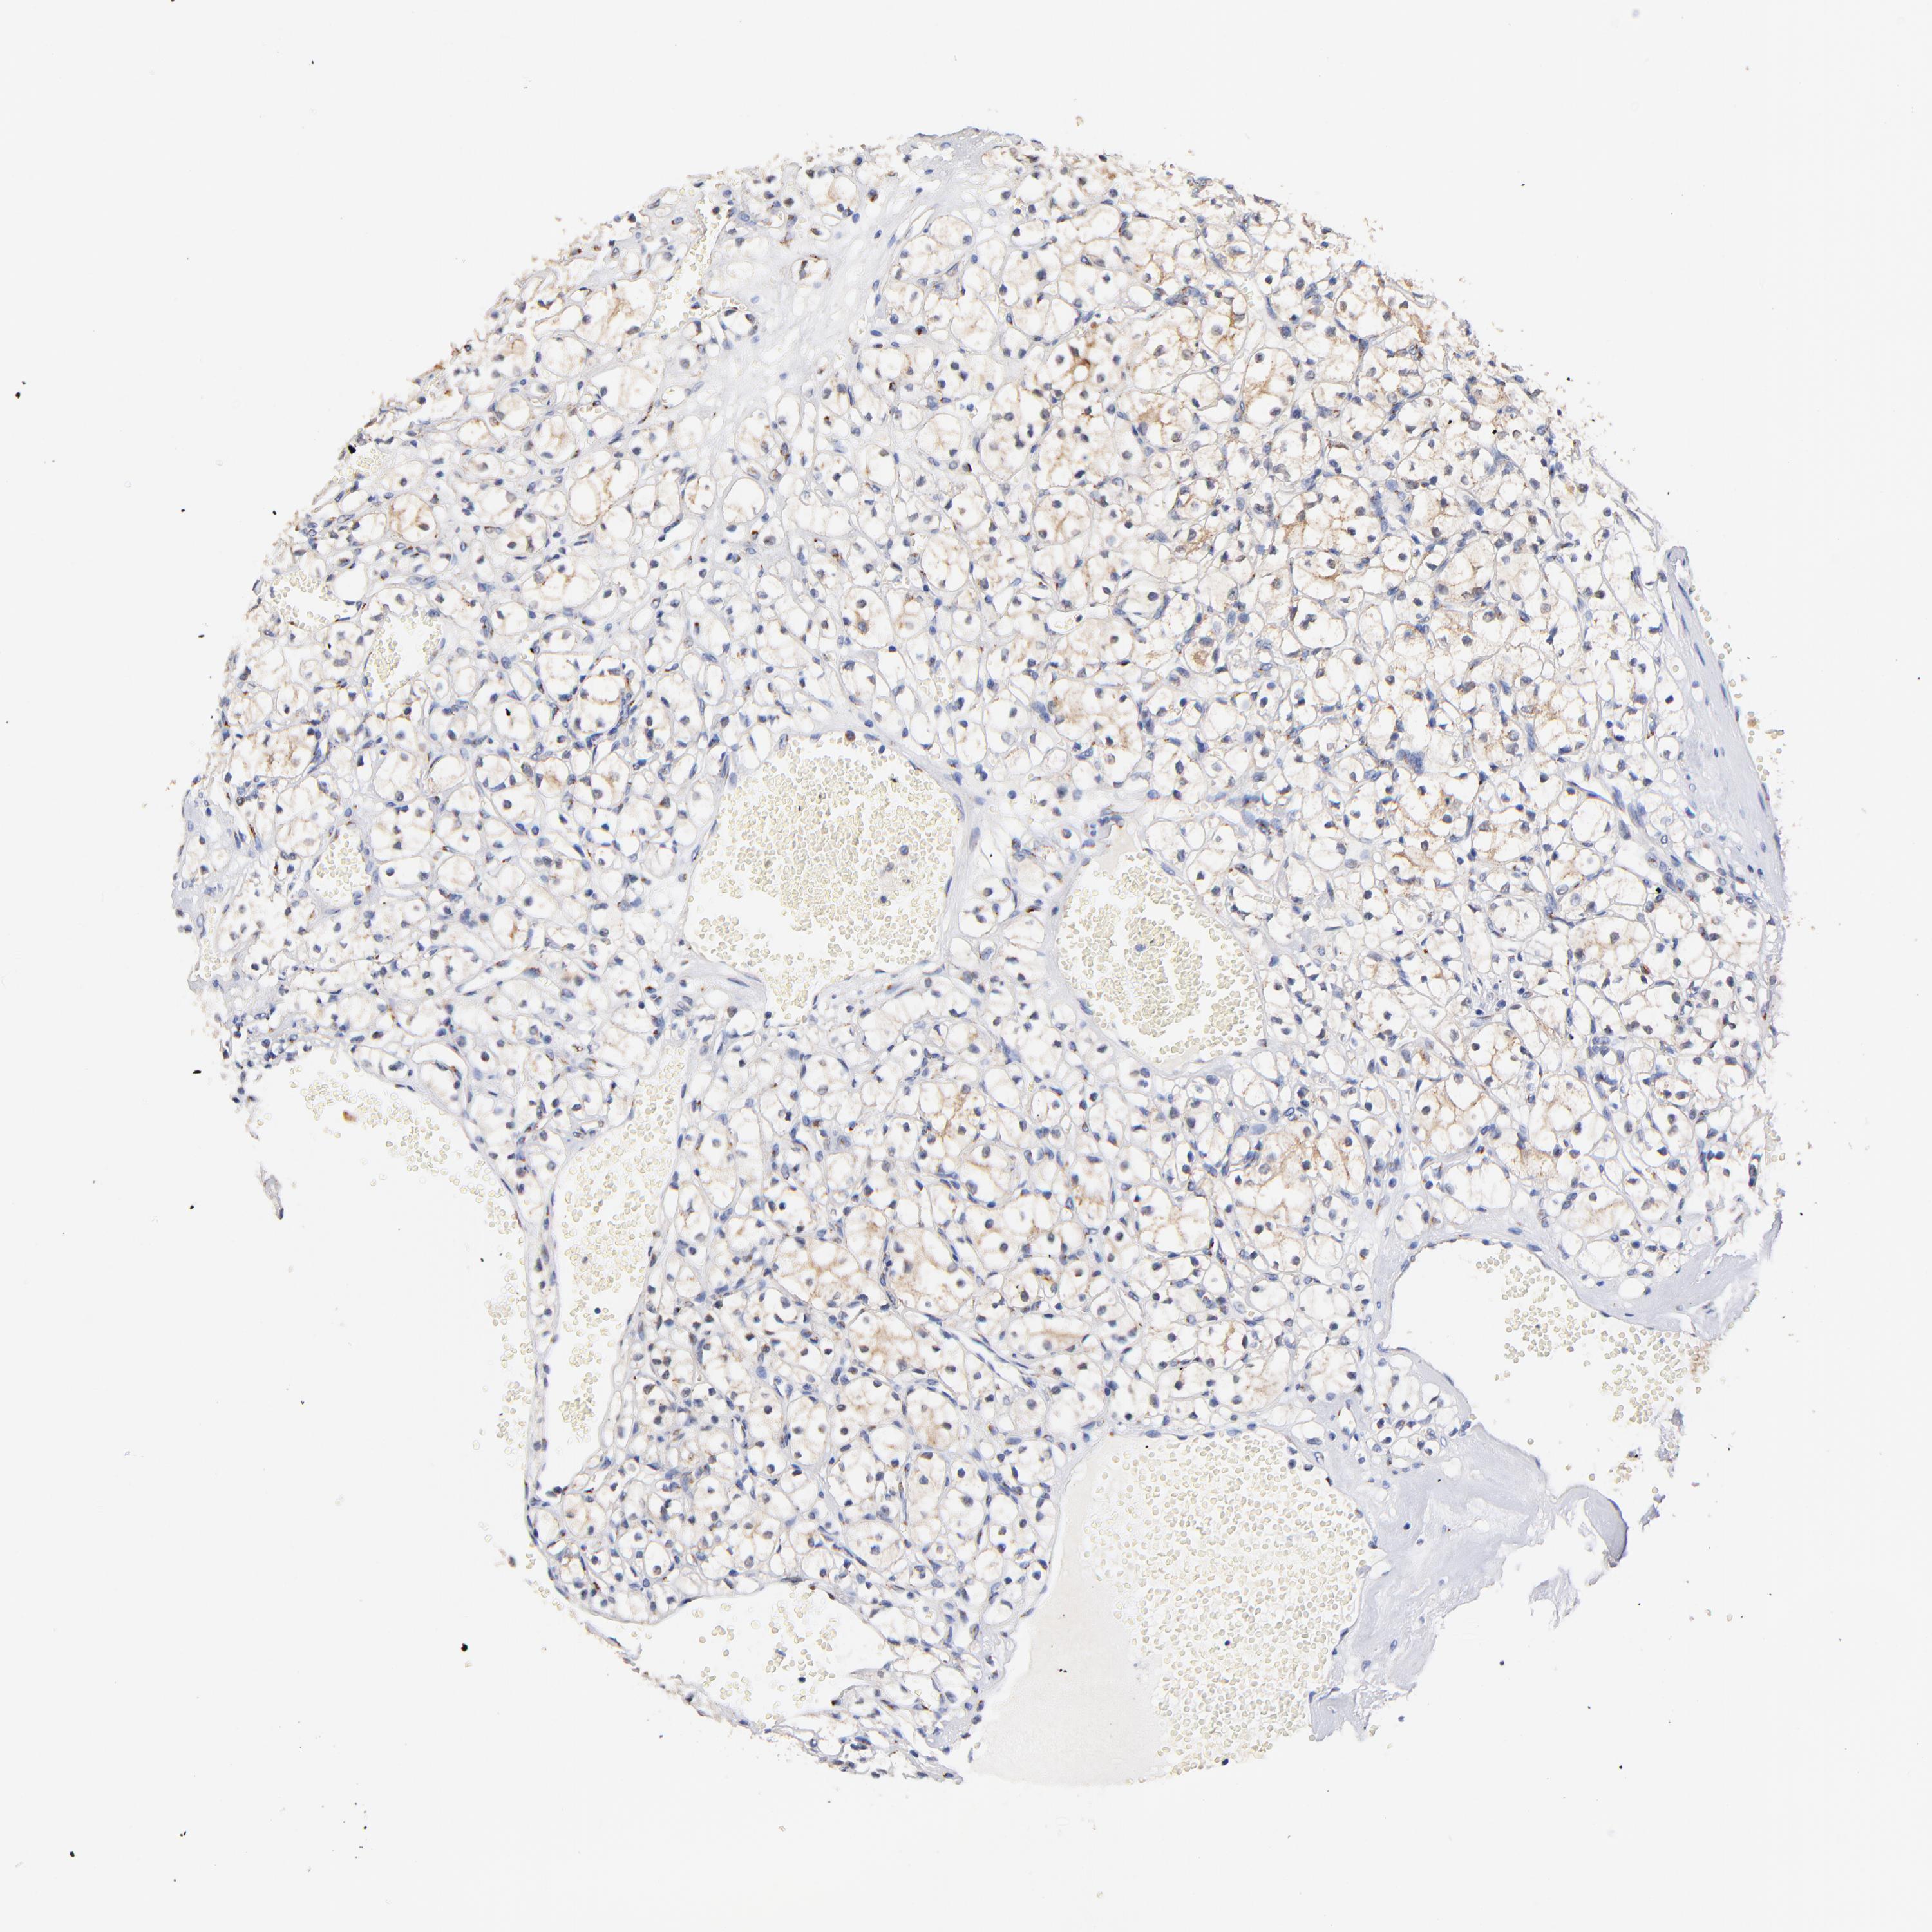

FMNL3 is validated prognostic, high expression is favorable in Kidney Renal Clear Cell Carcinoma (TCGA)

Best expression cut offi

Based on the FPKM value of each gene, patients were classified into two groups and association between prognosis (survival) and gene expression (FPKM) was examined. The best expression cut-off refers the FPKM value that yields maximal difference with regard to survival between the two groups at the lowest log-rank P-value. Best expression cut-off was selected based on survival analysis .

When clicking on this number, the vertical dashed line indicating cut-off, the interactive survival plot, and the Kaplan-Meier curve will be adjusted to show results based on the best expression cut-off.

: 9.77

P scorei

Log-rank P value for Kaplan-Meier plot showing results from analysis of correlation between mRNA expression level and patient survival.

N/A

5-year survival highi

5-year survival for patients with higher expression than the expression cutoff.

For melanoma and glioma, 3-year survival is shown.

5-year survival lowi

5-year survival for patients with lower expression than the expression cutoff.

Average pTPM 18.9

Number of samples 521